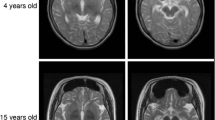

Variants in the WD repeat 45 (WDR45) gene in human Xp11.23 have recently been identified in patients suffering from neurodegeneration with brain iron accumulation, a genetically and phenotypically heterogeneous condition. WDR45 variants cause a childhood-onset encephalopathy accompanied by neurodegeneration in adulthood and iron accumulation in the basal ganglia. They have been almost exclusively found in females, and male lethality was suggested. Here we describe a male patient suffering from a severe and early neurological phenotype, initially presenting early-onset epileptic spasms in clusters associated with an abnormal interictal electroencephalography showing slow background activity, large amplitude asynchronous spikes and abnormal neurological development. This patient is a carrier of a 19.9-kb microdeletion in Xp11.23 containing three genes, including WDR45. These findings reveal that males with WDR45 deletions are viable, and can present with early-onset epileptic encephalopathy without brain iron accumulation.